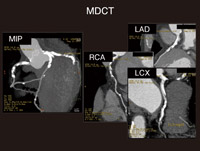

Amazon.co.jp: 心臓CTを活かす 新しい冠動脈疾患診断戦略。心臓CT実践ガイド | 診断と治療社。Vol.5 CTによる心臓検査の有用性と可能性。

Vol.5 CTによる心臓検査の有用性と可能性

Vol.5 CTによる心臓検査の有用性と可能性